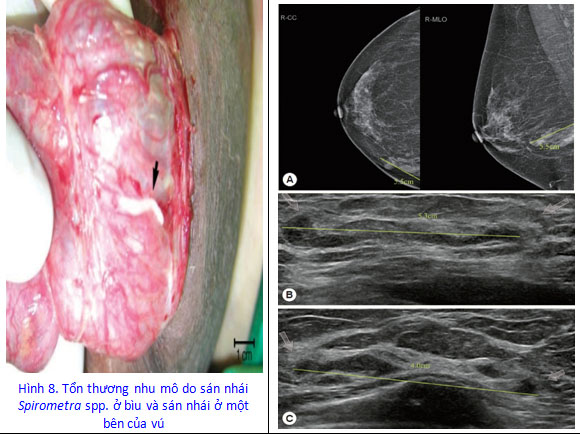

26.Hong S.J., Kim Y.M., Seo M., Kim K.S. Breast and scrotal sparganosis: sonographic findings and pathologic correlation. J. Ultrasound Med. Off. J. Am. Inst. Ultrasound Med. 2010;29(11):1627-1633.